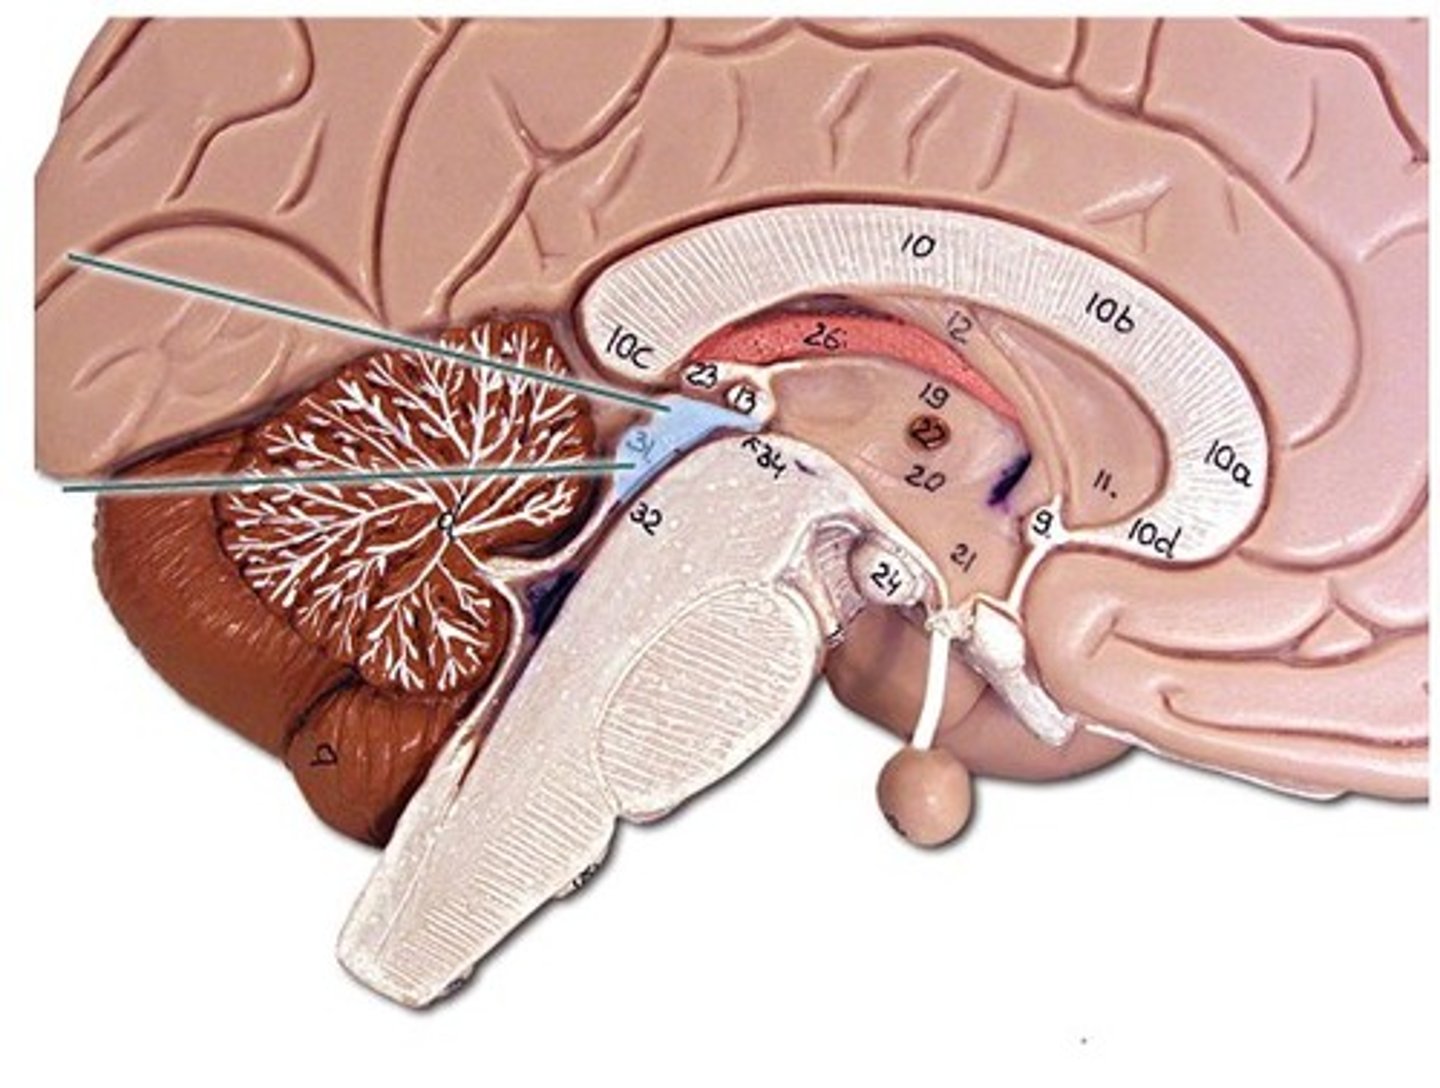

Corpus Callosum

Fibers connecting both halves of the brain, c shaped structure

Fornix

fiber tract linking limbic system regions

Diencephalon

made up of epithalamus, thalamus and hypothalamus

Thalamus

bilateral egg shaped nuclei connected by interthalamic adhesion and forming superior wall of 3rd ventricle. relay station for info coming from cortex.

Hypothalamus

forms floor of 3rd ventricle , cap over brain dtem and 3rd ventricle. Visceral control center, 3 fs

Cerebellum

"little brain" attach to the top of the brain stem. Components include vermis, arbor vitale, cortex, peduncles

Brain Stem

Continuation of spinal cord. Contains medulla oblongata, pons and midbrain

Septum Pellucidum

separates lateral ventricles

lateral ventricle

2 lateral ventricles. one in each cerebral hemisphere.

third ventricle

formed from diencephalon. Superior to hypothalamus; lies between right/left halves of thalamus

cerebral aqueduct

connects 3rd and 4th ventricle

fourth ventricle

runs through brain stem (midbrain) and becomes the central canal of the spinal cord.